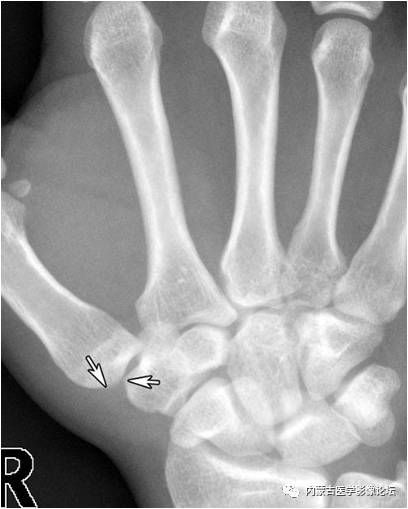

拇指掌腕关节“台阶征”:手正位片上(相当于拇指掌腕关节斜位),拇指掌腕关节的外形有一定程度的失真,关节边缘(箭)形成“台阶”样改变,与“半脱位”征象类似。手斜位片(相当于拇指掌腕关节正位)可以证实正位所见为假象。